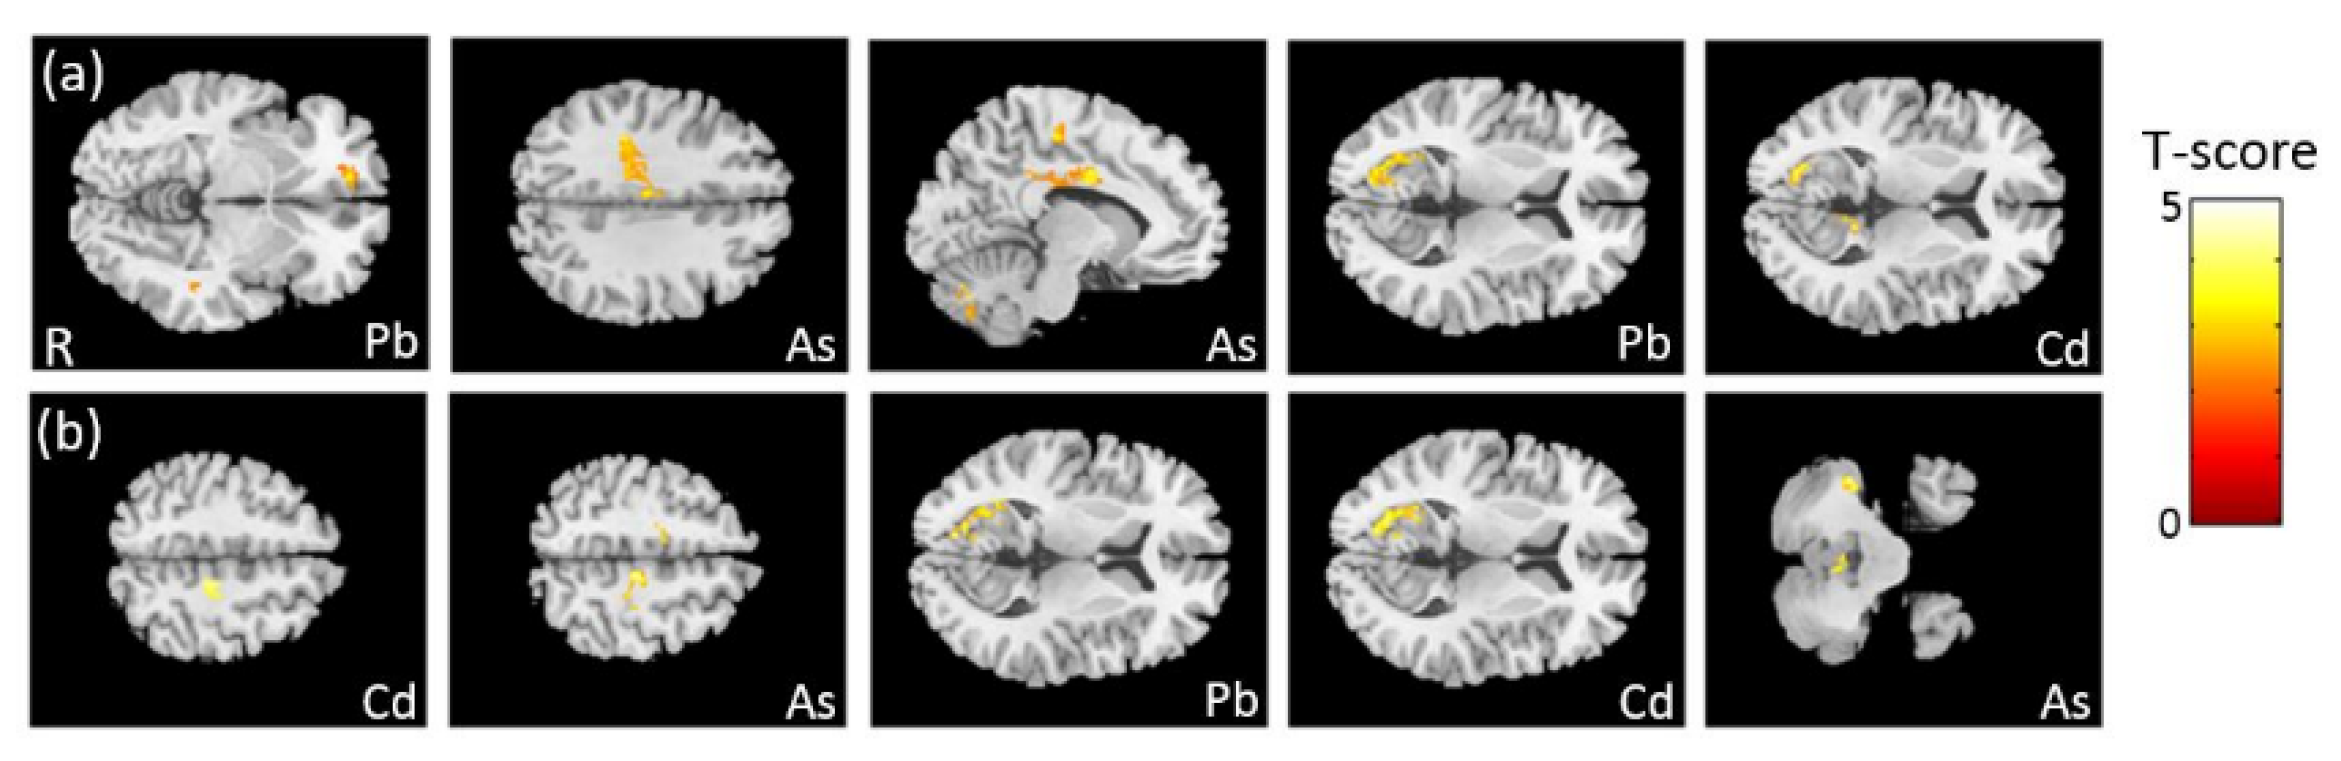

3.4. The Association between Heavy Metals and VBM

3.7. The Association Between Heavy Metals and GQI

4.3. Brain Volume and White Matter Structure Associated with Heavy Metals